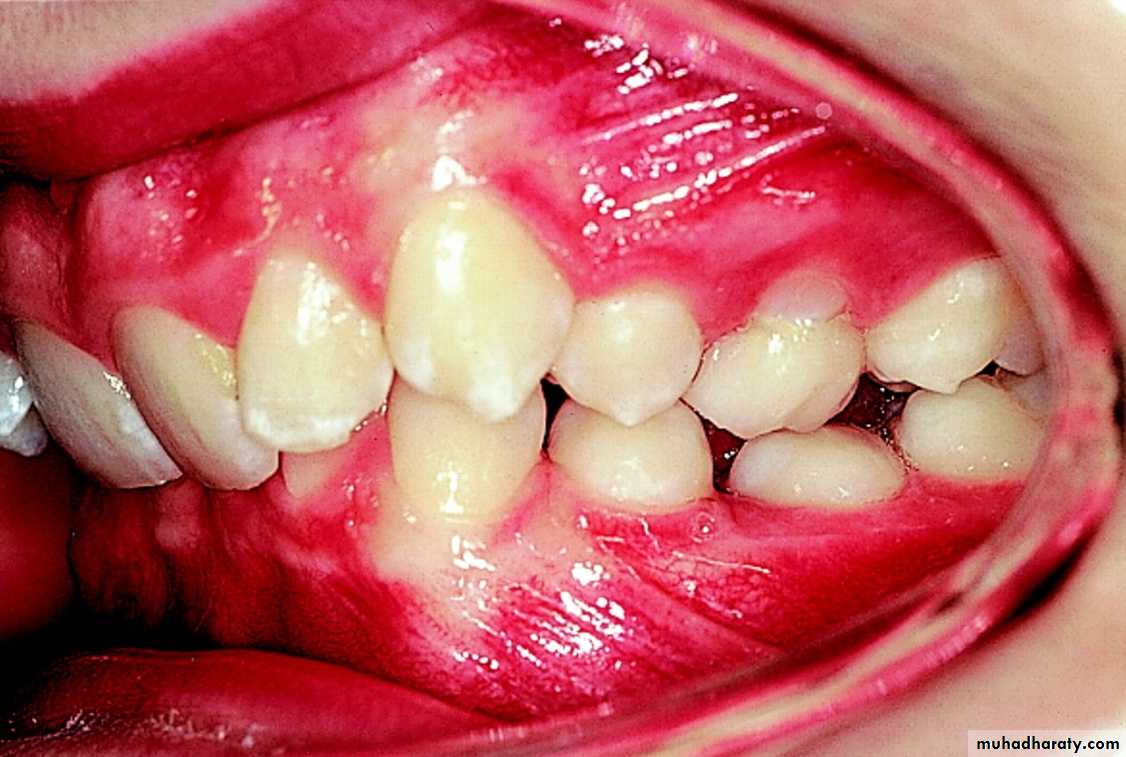

CLASS I MALOCCLUSIONTHE MESIOBUCCAL CUSP OF THE UPPER FIRST PERMANENT MOLAR OCCLUDES WITH THE MESIOBUCCAL GROOVE OF THE LOWER FIRST MOLAR, BUT LINE OF OCCLUSION IS INCORRECT BECAUSE OF MALPOSED TEETH, ROTATIONS OR OTHER DISCREPANCIES.

CLASS II MALOCLUSION

THE MESIOBUCCAL CUSP OF THE LOWER FIRST PERMANENT MOLAOCCLUDES DISTAL TO THE CLASS I POSITION.Condition when class II molar relationship is present with proclined upper central incisors.

There is an increase in overjet.

CLASS II DIVISION 1